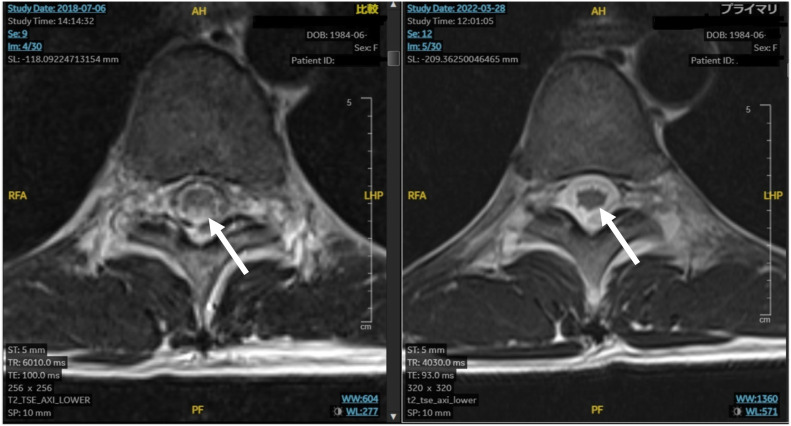

亚急性脊髓病是甲氨蝶呤(MTX)的一种罕见但严重的并发症,可导致截瘫。尽管其潜在机制尚未完全阐明,但同型半胱氨酸被认为在这一不良反应的发病机制中发挥了作用。在此,我们报告了一例 34 岁的弥漫大 B 细胞淋巴瘤女性患者,在接受改良的 CODOX-M/IVAC 方案(包括大剂量静脉注射 MTX 和鞘内(IT-)MTX)治疗后出现进行性截瘫,并伴有膀胱和排便功能障碍。在接受 S-腺苷蛋氨酸、蛋氨酸、氰钴胺和叶酸的联合治疗后,神经症状在发病后 4.5 个月内逐渐改善至基本正常水平。在化疗期间,包括治疗血液恶性肿瘤的大剂量 MTX 和 IT-MTX,应仔细评估 MTX 引起的亚急性神经元损伤,并尽早开始适当的治疗。

Subacute myelopathy is a rare but serious complication of methotrexate (MTX) that may cause paraplegia. Although its underlying mechanisms have not been fully elucidated, homocysteine is thought to play a role in the pathogenesis of this adverse effect. Herein, we report the case of a 34-years old female patient with diffuse large B-cell lymphoma who developed progressive paraplegia accompanied by dysfunctional bladder and bowel movements after treatment with a modified CODOX-M/IVAC regimen, including high-dose intravenous MTX and intrathecal (IT-) MTX. Neurological symptoms gradually improved to almost normal levels within 4.5 months of onset following treatment with a combination of S-adenosylmethionine, methionine, cyanocobalamin, and folate. During chemotherapy, including high-dose MTX and IT-MTX for hematological malignancies, MTX-induced subacute neuronal damage should be carefully evaluated, and appropriate treatment should be initiated as early as possible.